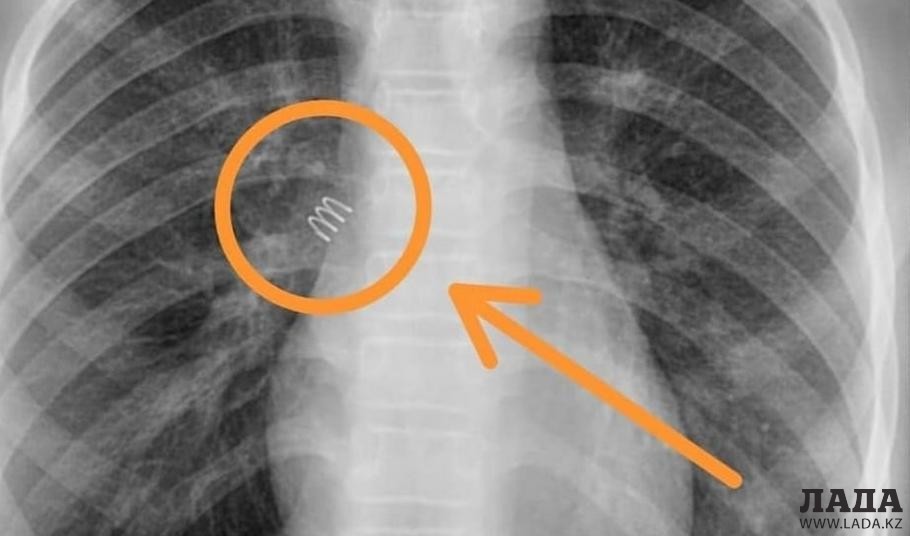

Металлическую пружину из бронхов удалили 11-летней девочке в Актау

Пружина от шариковой ручки находилась в бронхах ребенка 11 месяцев. Операция по удалению инородного тела прошла успешно. Об этом сообщили в клинике «SOFIE MEDGROUP».

Операция по извлечению металлической пружины от шариковой ручки размером два сантиметра длилась 40 минут.

- Благодаря слаженной работе команды в составе детского хирурга областной детской больницы Орынбая Жалгасбаевича, одного из ведущих анестезиологов и ведущего эндоскописта многопрофильной клиники «SOFIE MEDGROUP» Роллана Елеусинова, из бронхов 11-летней пациентки после 11-месячного пребывания в бронхах была изъята металлическая пружина от шариковой авторучки длиною в два сантиметра. Состояние девочки стабильное, - сообщили в клинике «SOFIE MEDGROUP».